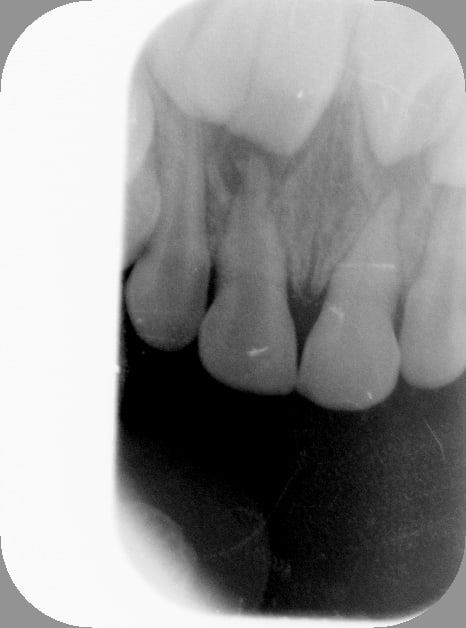

Tiens, je viens de faire ça il y a 5 min, ça me semblait à propos.

Petite vue en mars 2013, 51 dyschromiée suite à chute, 3 ans et demi à l'époque, je la sentais un peu jeune pour tenter le coup.

Pas d'image apicale, pas de fistule.

Revue ce jour, avec les frangines: apparition d'une fistule, décision de l'endo, faite en 5 min. Gamine super cool, pas eu besoin d'anesthésie. 4 ans et 11 mois ce jour. Ordonnance d'antibio en cas de réveil infectieux dans les jours à venir.

Obturation Sealite+IRM dans la chambre, ça tiendra jusqu'à la chute de la dent.